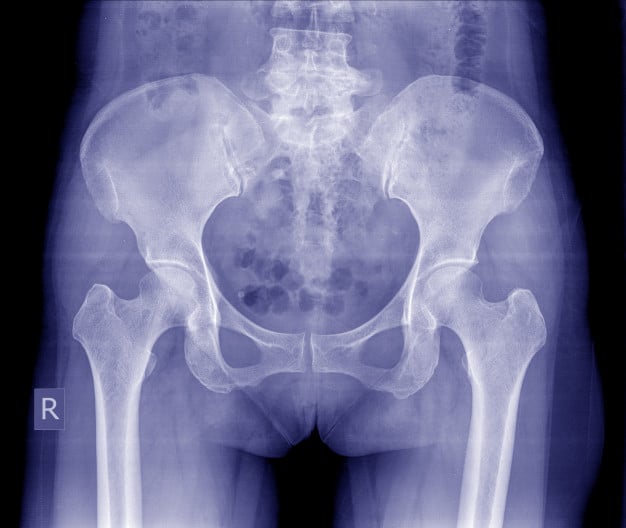

La mutilación genital femenina

La mutilación genital femenina Read More »

Más de 200 millones de niñas y mujeres han sido víctimas de la mutilación genital femenina alrededor del mundo., según datos de UNICEF.

La mutilación genital femenina Read More »